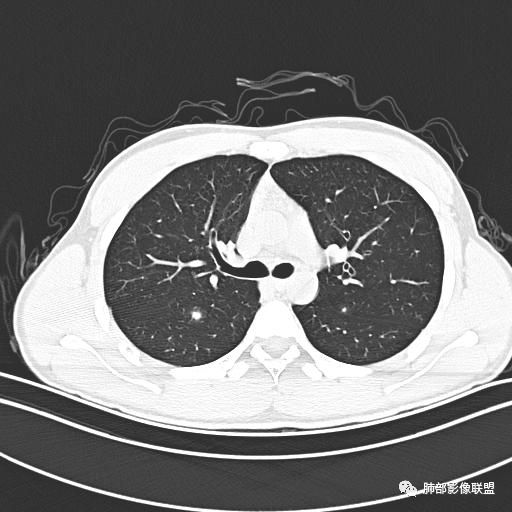

小强:青年,发热,皮疹;双肺散在结节,周围磨玻璃,点晕征,疱疹病毒感染,鉴别荚膜组织胞浆菌,结核。 大雄:青年,急性起病,发热伴全身皮疹2天,抗病毒治疗体温有下降。双肺随机分布大小不等类圆结节,“点晕征”。考虑水痘-疱疹病毒(VZV)血播询问接触史,查体皮疹分布以及形态基本可诊断。 王开金江津中心医院呼吸科:青年男性,起病急,病程短,以发热,皮疹为首发症状,感染指标以单核细胞升高为主,胸部ct双肺多发结界,周围有晕,点晕表现,随机分布,同意於老师意见,水痘疱疹病毒血流感染累及肺。 王秀仙:双肺多发大小不等结节,周围有晕,边缘模糊,呈点晕征表现。青年,急性起病,发热伴全身皮疹2天,抗病毒治疗体温有下降。考虑疱疹病毒。鉴别荚膜组织胞浆菌。 傅昌瑜:19岁男性,发热、全身皮疹2天,单核细胞增高,双肺多发结节,结节边缘见边界不清磨玻璃影。点晕征+发热、全身皮疹+单核细胞增高——考虑水痘-带状疱疹病毒肺炎。 一切∮随缘:年轻男性,发热,皮疹两天,实验室,CRP,PCT增高,影像:双肺多发散在磨玻璃结节,边界欠清,大小不等,呈点晕征改变,以血管束周围分布为主,局部血管束略增粗,其它无明显改变,考虑:1:病毒性肺炎(水痘疱疹病毒?不知道皮肤有无改变)2:真菌(组织胞浆菌,血管侵袭性肺曲霉)3:GPA4:寄生虫(实验室没有看到嗜酸细胞增高) 赵山河:双肺散在结节,周围有晕,边缘模糊,呈点晕征表现。青年,急性起病,发热伴全身皮疹2天,抗病毒治疗体温有下降。考虑水痘—疱疹病毒感染。洪桥爱:青年男性,发热、皮疹2天,伴瘙痒,皮疹于面部首发,之后进展至全身,虽然没有对皮疹进行描述,但是从出疹时间及皮疹进展情况,伴瘙痒,应该就是个水痘患者;CT提示双肺随机分布结节影,部分结节伴有边界不清晕征,考虑水痘血播肺。 刘强:年轻男性,急性起病,皮疹,发热,抗感染治疗体温下降,说明有效。影像表现为散在点晕征,感染类疾病谱(疱疹病毒,真菌,结核),结合年龄,皮肤皮疹,考虑水痘-疱疹病毒性肺炎。 小兜:男性,19岁,发热皮疹两天,颜面部至全身,CRP,降钙素及单核增高。CT示双肺散在小结节,周围伴磨玻璃影,点晕征,考虑为水痘-带状疱疹病毒(varicella-zoster virus,VZV)肺炎 必有路:青年,皮疹+发热+“点晕征”→水痘-疱疹病毒(VZV) 许慧良:青年男性患者,发热、皮疹2天,体温最高38.5℃,第3天皮疹扩展至全身,伴瘙痒,胸部CT:双肺多发随机分布的小结节,结节周边见边界模糊的晕征,考虑水痘病毒感染流心明智:男,19,急性起病,发热伴全身皮疹2天。出疹顺序头→全身,抗病毒有效。胸部CT:两肺多发大小不等类圆形实性小结节影,随机分布,结节周围环绕GGO,边界模糊,呈点晕征。出疹特点是关键,未提示。考虑:血播病毒性肺炎,水痘-疱疹病毒?麻疹?鉴别荚膜组织胞浆菌、TB、血管炎、寄生虫等。 浪迹天涯:病灶多为5-10mm大小结节,结节周围可见磨玻璃样的晕环,常多发,可分布于肺内任何区域,考虑水痘—带状疱疹病肺炎如果短时间内有新的一个区域浸润,更加能说明,